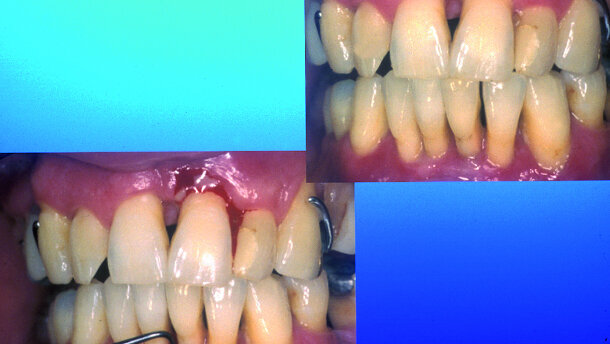

Methodik zweiter Therapieschritt

Es sollte wie folgt vorgegangen werden: Nach dem ersten Schritt, der sorgfältigen Entfernung des supraund subgingivalen Zahnsteins einschließlich Motivation des Patienten während etwa drei bis vier jeweils circa einstündigen Sitzungen durch die Dentalhygienikerin, erfolgt mit einem zweiten Schritt die Phase der eigentlichen Taschenelimination. Diese wird als gewebeschonende geschlossene Kürettage mittels Gracey- Finierküretten (z.B. American Eagle) durchgeführt. Die Wurzeloberflächen aller Parodontien des Ober- und Unterkiefers werden in Abhängigkeit von der Sondierungstiefe jeweils fünf- bis 30-mal in einer oder spätestens einer zweiten Sitzung am nächsten Tag geglättet. Mit der stumpfen Kürettenseite erfolgt simultan die schonende Weichgewebskürettage zur Entfernung des entzündlichen Granulationsgewebes (Abb. 3a–c).

Dieser zweite Schritt wird zwingend handinstrumentell durchgeführt, denn durch die maschinenbetriebene Wurzelglättung, einschließlich Wasserkühlung, kommt es zur Störung des Blutkoagulums im kapillären Spalt Zahnfleischtasche/Zahnwurzel. Da ein gut organisiertes Blutkoagulum die Basis für jeden Wundheilungsvorgang ist, wird nur so auch das Reattachment und somit der „Taschenverschluss“ gefördert. Zutritt von Wasser bzw. Speichel stört das Koagulum im Taschenspalt und fördert die innere epitheliale Ausscheidung der Zahnfleischtasche. Um die fibrinolytische Aktivität des Speichels zu minimieren, werden alle Patienten nach dem zweiten Schritt im Oberund Unterkiefer mit einem Wundverband (VOCOpac®) versorgt. Die adjuvante Antibiose erfolgt bei schwerer chronischer Parodontitis mit 2 x 600 mg Clinda-saar® für acht Tage und bei aggressiver Parodontitis mit Metronidazol 2 x 500 mg Vagimid für acht Tage. Die Kontrolluntersuchungen werden im ersten Halbjahr alle vier Wochen, danach alle zwölf Wochen und vom 24. bis zum 48. Monat halbjährlich durchgeführt. Röntgenologische Kontrollaufnahmen sollten nach und 48 Monaten erfolgen (Abb. 4 a–b).